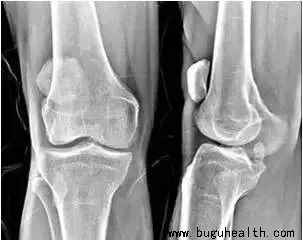

有文章提及,髌骨软化症是膝关节损伤中的常见软组织损伤疾病,其发病率在2743名普通人群中高达36.2%。该病以膝关节疼痛为主,以爬楼梯和下蹲痛的临床表现最为显著,对患者日常工作和生活带来严重干扰。尤其是在30-40岁年龄段是髌骨软化症高发年龄,在此年龄段膝关节软骨已开始退变,而此时工作和日常生活也是很繁忙的,所以易加重髌股关节损伤和劳损,如能及时积极地采取防治措施,对防止其发展为全膝骨关节炎是有好处的。

1.髌骨软化症与股骨滑车的形态有相关性。股骨滑车的形态影响着它对髌骨的控制能力。正常情况下,股骨内外侧髁外高内低的结构对髌骨进行了有效的阻挡,使髌骨可以沿股骨滑车沟正常运动,当股骨外侧髁发育异常低平时则不能起到有效的限制作用,这时髌骨在股四头肌外侧头作用下向外发生偏移甚至脱位,发生髌股轨迹异常,长时间的运动轨迹异常造成髌股关节压力不平衡及局部应力改变,长期的压力不平衡及应力改变是引起髌股软骨病理性改变的重要原因,长此以往将增加髌骨软化症发生风险。

4.另外研究表明髌骨软化症患者的髌骨倾斜角较正常志愿者增加,这种结构变异直接导致了髌骨的外偏,进而导致髌骨轨迹异常。当髌骨倾斜超过正常范围后,导致髌骨并不能按照正常运行轨迹运动,过度的髌骨倾斜导致髌骨外移趋势增加,而内移的趋势减小,增加了髌骨外侧关节软骨面负荷,长时间的运动轨迹异常将会导致髌骨外侧应力区域软骨磨损加重并导致软骨破坏、脱落,最终导致髌骨软化症。